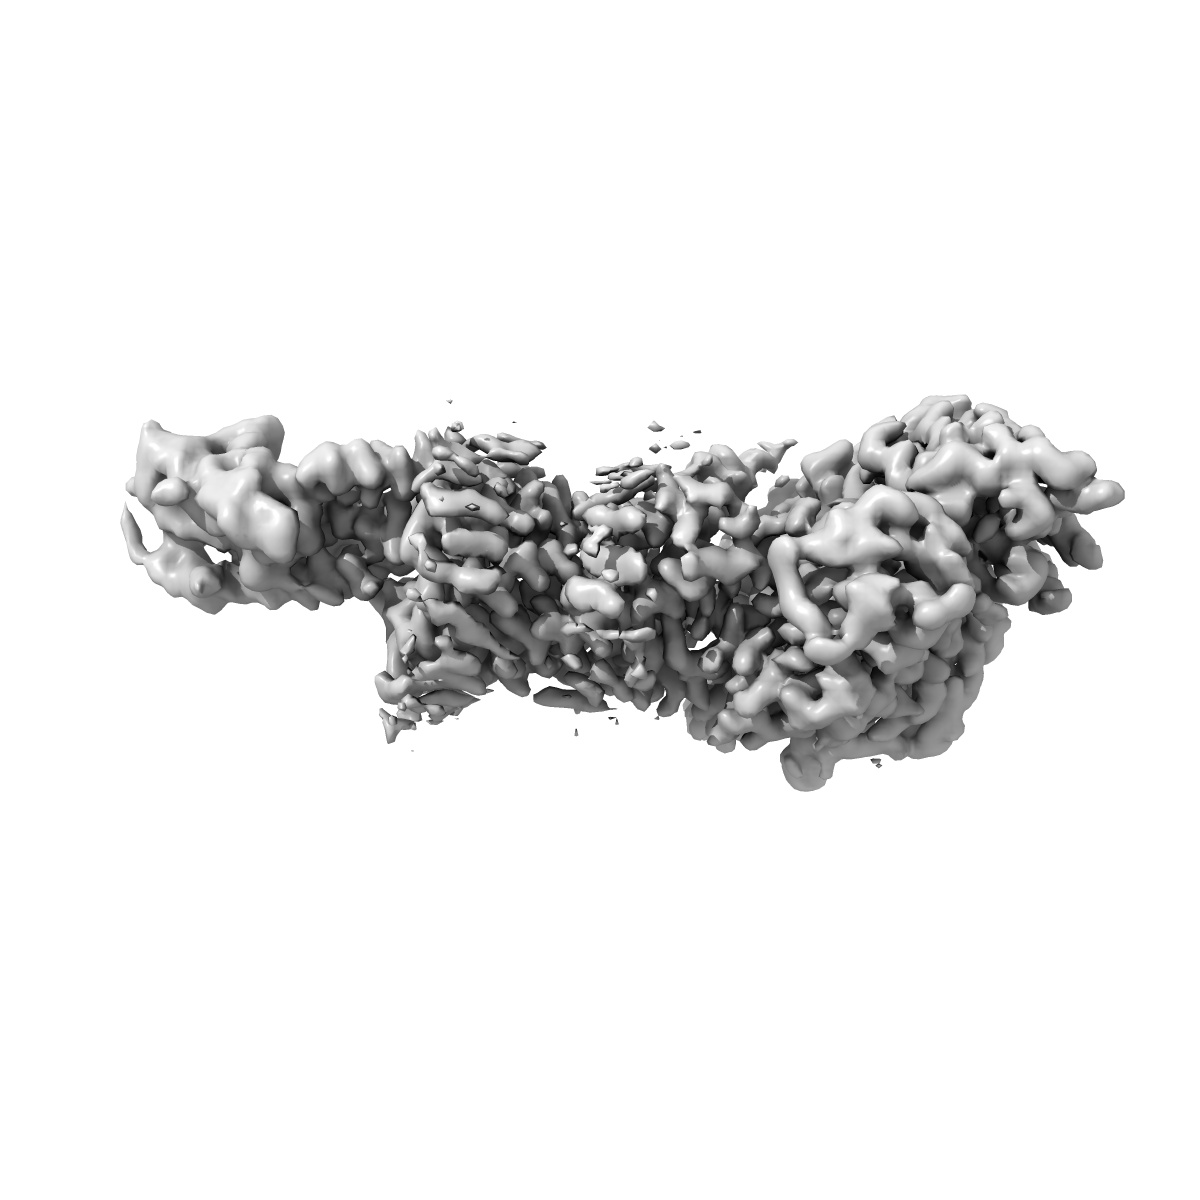

Cryo-EM structure of the GLP-1R/GCGR dual agonist MEDI0382-bound human GCGR-Gs complex

Single-particle2.91 Å

Sample: Cryo-EM structure of the GLP-1R/GCGR dual agonist MEDI0382-bound human GCGR-Gs complex

Structural analysis of the dual agonism at GLP-1R and GCGR.

(2023) PNAS , 120 , e2303696120 - e2303696120